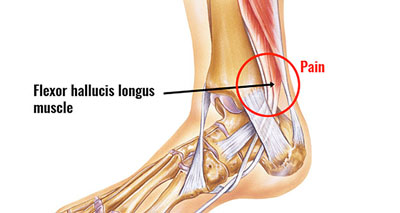

Posterior Tibial Tendonitis Signs and Treatment

Inside Ankle Pain Medial Symptoms Causes Treatment Rehab

4 Ways to Prevent and Treat Posterior Tibial Tendonitis Runners

Inside Ankle Pain Medial Symptoms Causes Treatment Rehab

Running with Pain on the Inside of the Ankle Physiotherapy